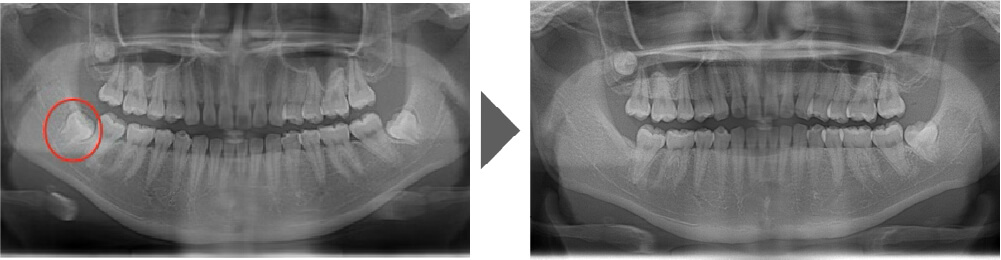

抜歯症例⑤

完全に生えているわけではありませんが、 手前の7番目の歯と密着しており、 虫歯のリスク非常に高いため抜歯いたしました。

【抜歯所要予約時間】

各15分

(麻酔の時間があるので処置自体はもっと短いです)